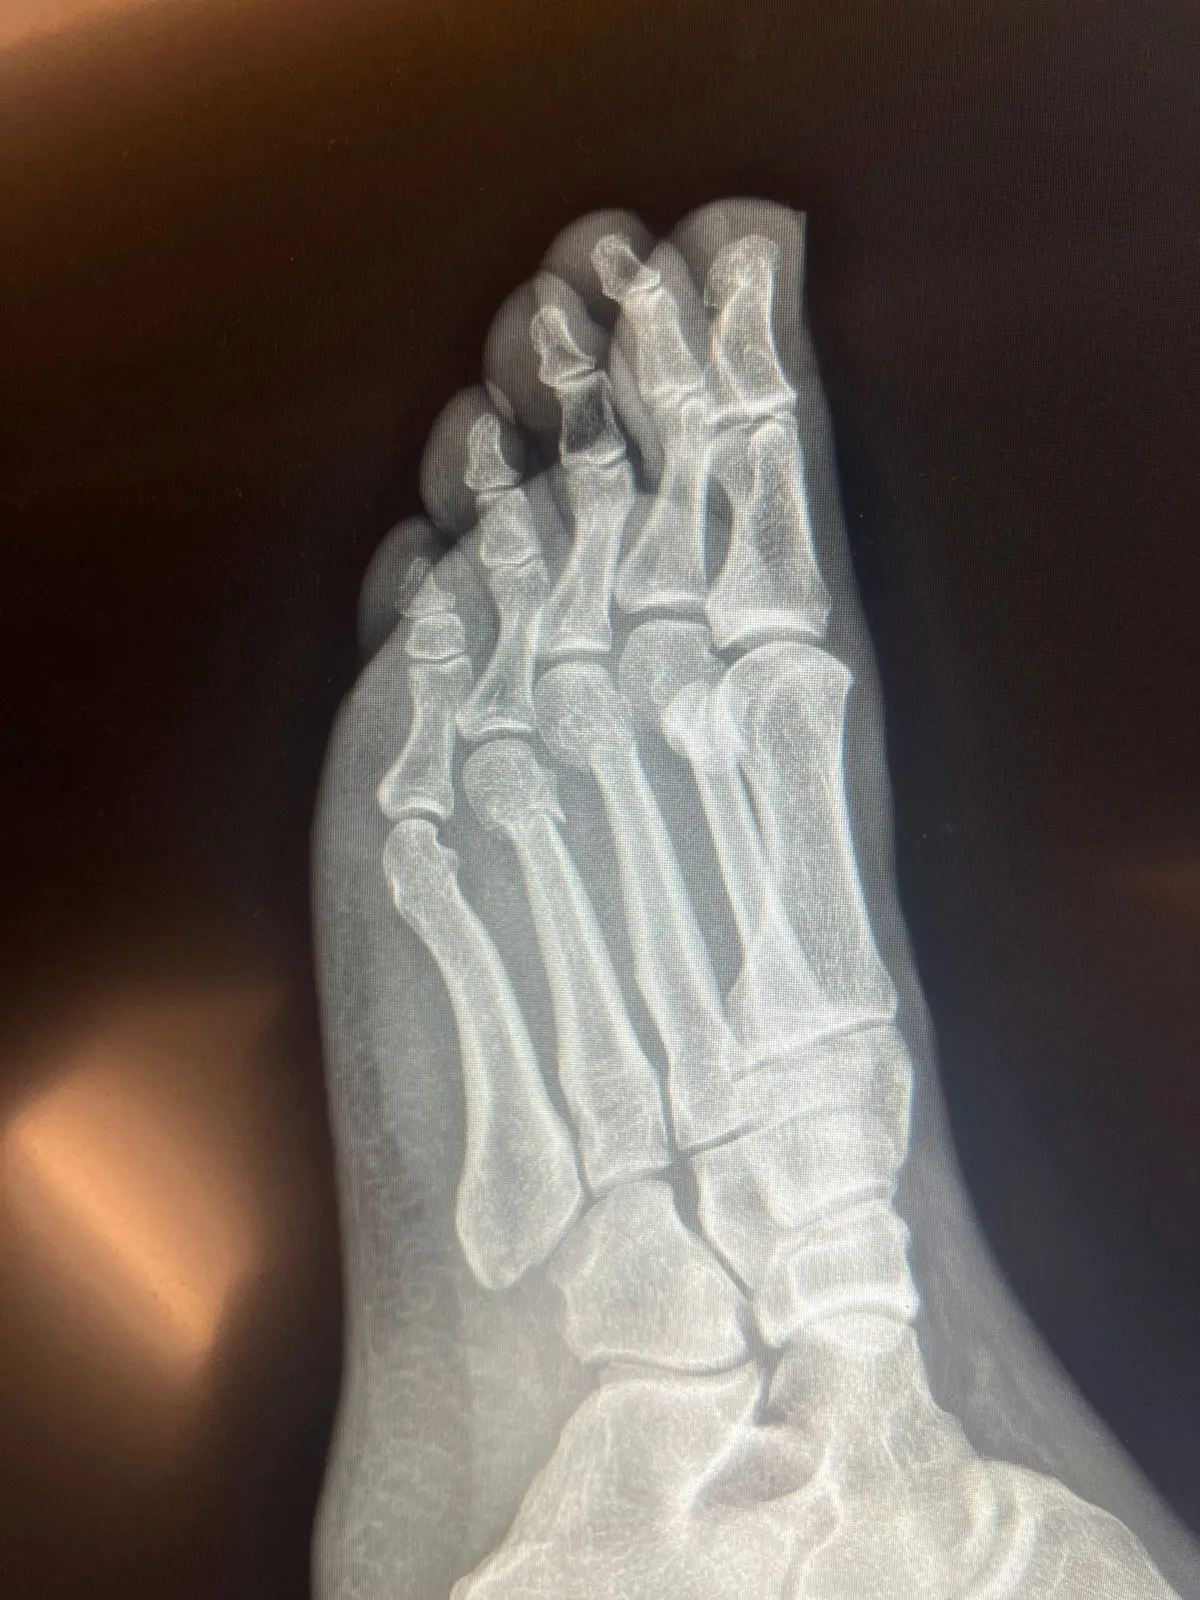

CHP Lideri Özgür Özel’in kırılan ayağının tomografisini yayınladığı görüntüler bile günlerce tartışılacak bir meseleye dönüşüyor. Çiftçilerin isyanı, işçilerin direnişi, emeklilerin, öğretmenleri, mali müşavirlerin, gençlerin ve kadınların itirazları ise yine aynı isimlerin çizdiği çerçevelerde tartışılıyor.

Öyle ki CHP Lideri Özgür Özel’in kırılan ayağının tomografisini yayınladığı görüntüler bile günlerce tartışılacak yegâne meseleye dönüşüyor. Çiftçilerin isyanı, işçilerin direnişi, emeklilerin, öğretmenleri, mali müşavirlerin, gençlerin ve kadınların itirazları ise yine aynı isimlerin çizdiği çerçevelerde tartışılıyor. Konuların öznelerinin yer almadığı, sorunların muhataplarına söz hakkı dahi verilmediği bir dizi program sürdürülüp gidiyor. Böylelikle halkın sorun ve taleplerini tartışmaya açacak gündemlerden çok polemik yaratacak, kişiler üstünden ilerleyen gündemler kendine daha çok yer buluyor.